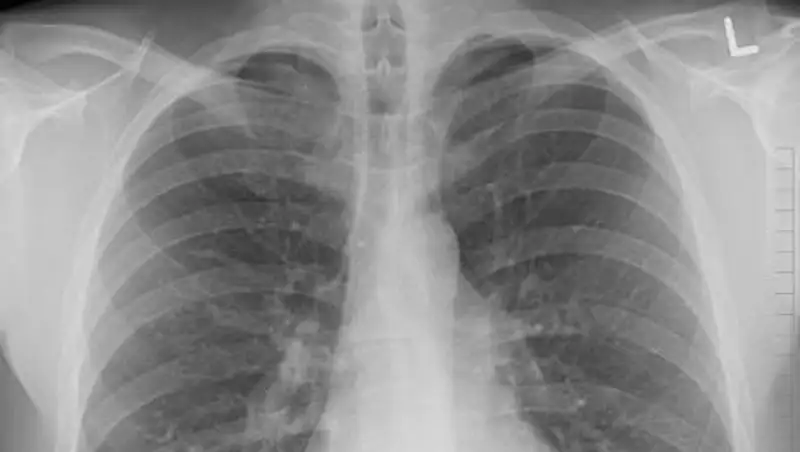

100 человек заболели пневмонией за сутки в Казахстане

100 человек заболели пневмонией за сутки в Казахстане, один летальный исход, сообщает zakon.kz.

На 21 января зафиксированы 100 случаев заболевания пневмонией с признаками коронавирусной иxнфекции, 1 летальный исход и 74 человека выздоровели, - сообщили в министерстве здравоохранения.

Всего с 1 августа зарегистрировано: заболевших – 47311, летальных случаев - 550, выздоровевших - 35055.